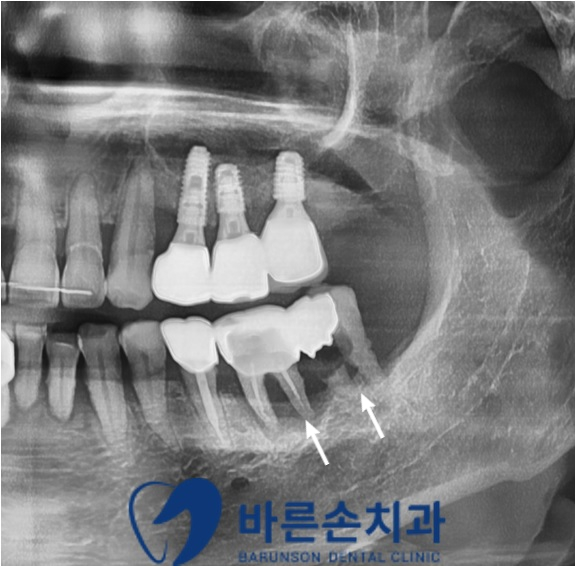

우선 불편감의 원인을 정확하게 알기 위해 파노라마 촬영을 시행하였습니다

파노라마 확인 결과 아래 어금니 두 곳에

염증으로 인한 치조골(뼈) 손상과 치아우식이 보이고

이로 인한 치아의 손상도가 크기 때문에

뼈이식과 함께 임플란트 수술이 필요해 보였는데요